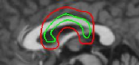

Refer to captionRefer to captionRefer to caption(a)(b)(c)Refer to captionRefer to captionRefer to caption𝑎𝑏𝑐\begin{array}[]{ccc}\includegraphics[width=72.26999pt]{tumor-init.pdf}&\includegraphics[width=72.26999pt]{tumor.pdf}&\includegraphics[width=72.26999pt]{tumor-edge.pdf}\\ (a)&(b)&(c)\end{array}

Figure 16: (a) Initialization with ring template, (b) converged snake and (c) edge detector output of image.

We next develop templates for objects with hole(s) in their structure. These templates are called ring templates. Figures 15 and 16 show examples of ring templates. The area enclosed between the red contours act as region 1subscript1\Re_{1} and the area between the green contours is region 0subscript0\Re_{0}. Figure 17 shows the construction of the ring contours. The two seemingly unconnected contours are actually one connected contour. Hence, partial derivative calculations in equation (26) are still valid.

In Figure 15, the ring template has been used for segmenting the left ventricular (LV) wall of heart in cardiac MR images. Another example is shown in Figure 16. The template used in both examples has a greater thickness in the inner ring-shaped annular region than the outer annular region. This was done to facilitate obtaining the desired object’s structural information by means of the contrast (for example, between the endocardium and the LV wall) that a good initialization can offer. Hence, while designing a template, we can incorporate prior knowledge of the object and its surroundings.